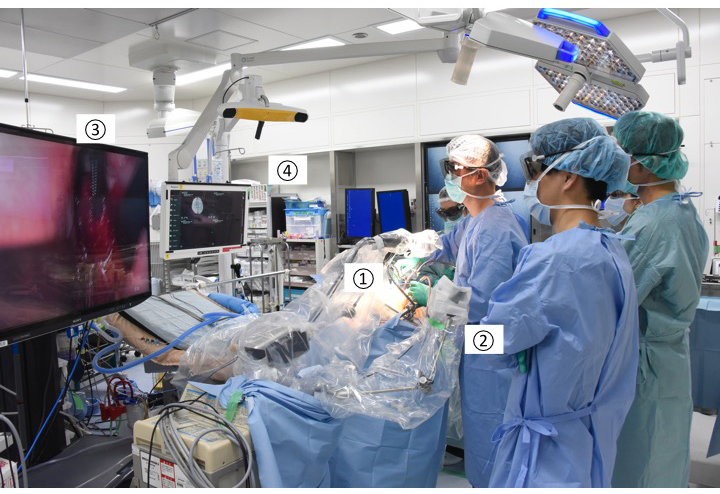

Under general anesthesia, the patient was positioned supine on the operating table with head fixed in a Mayfield head clamp. A neuronavigation system (iPlan Cranial software; Brainlab AG, Feldkirchen, Germany) was introduced to the surgical field. We made a small bicoronal skin incision around the bregma. With four burr holes, placed 3 cm anterior, 2 cm posterior, 3 cm to the right, and 3 cm to the left of the bregma, craniotomy was performed, then a wide U-shaped dural flap was made on the right side. We did not minimize the skin incision and craniotomy for use of the exoscope in case we needed to switch to using the microscope. Retractor blades were set over the cortex and falx, exposing the inferior falx and cingulate gyri. At this time, the 4K-3D surgical monitor was placed caudal to the patient and in front of the operator. All medical staff wore surgical 3D glasses, and performed the steps while viewing the same images (Fig. 1).

Fig. 1.

Fig. 1.Intraoperative setup for exoscopic corpus callosotomy. The VITOM 3D exoscope ① is positioned cranial to the patient. ② Controller of the camera and other systems. ③ The 4K-3D surgical monitor. ④ Neuronavigation system.